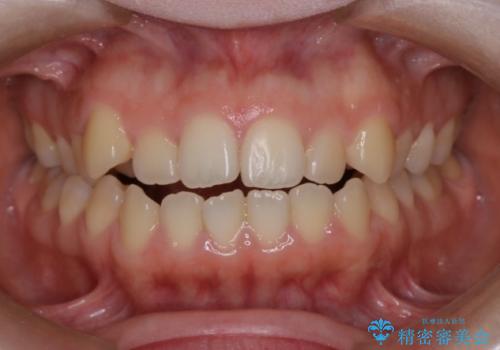

- 口元の突出感は気にならないが、上の前歯の角度と、下の前歯のがたつきが気になるとご相談にいらした方です。なるべく費用や治療期間を抑えて治療したいとのご希望に合わせて治療を計画しました。

この患者様への治療方針として、奥歯から少しずつ歯を移動させる方法と、歯をわずかに削って並べる方法とをご提案しました。短期間での治療を望まれたため、歯をサイズダウンさせて歯を並べました。わずかではあるものの、削った歯は元には戻せないことを十分ご説明し、ご理解ご了承を頂いた上で治療を行いました。